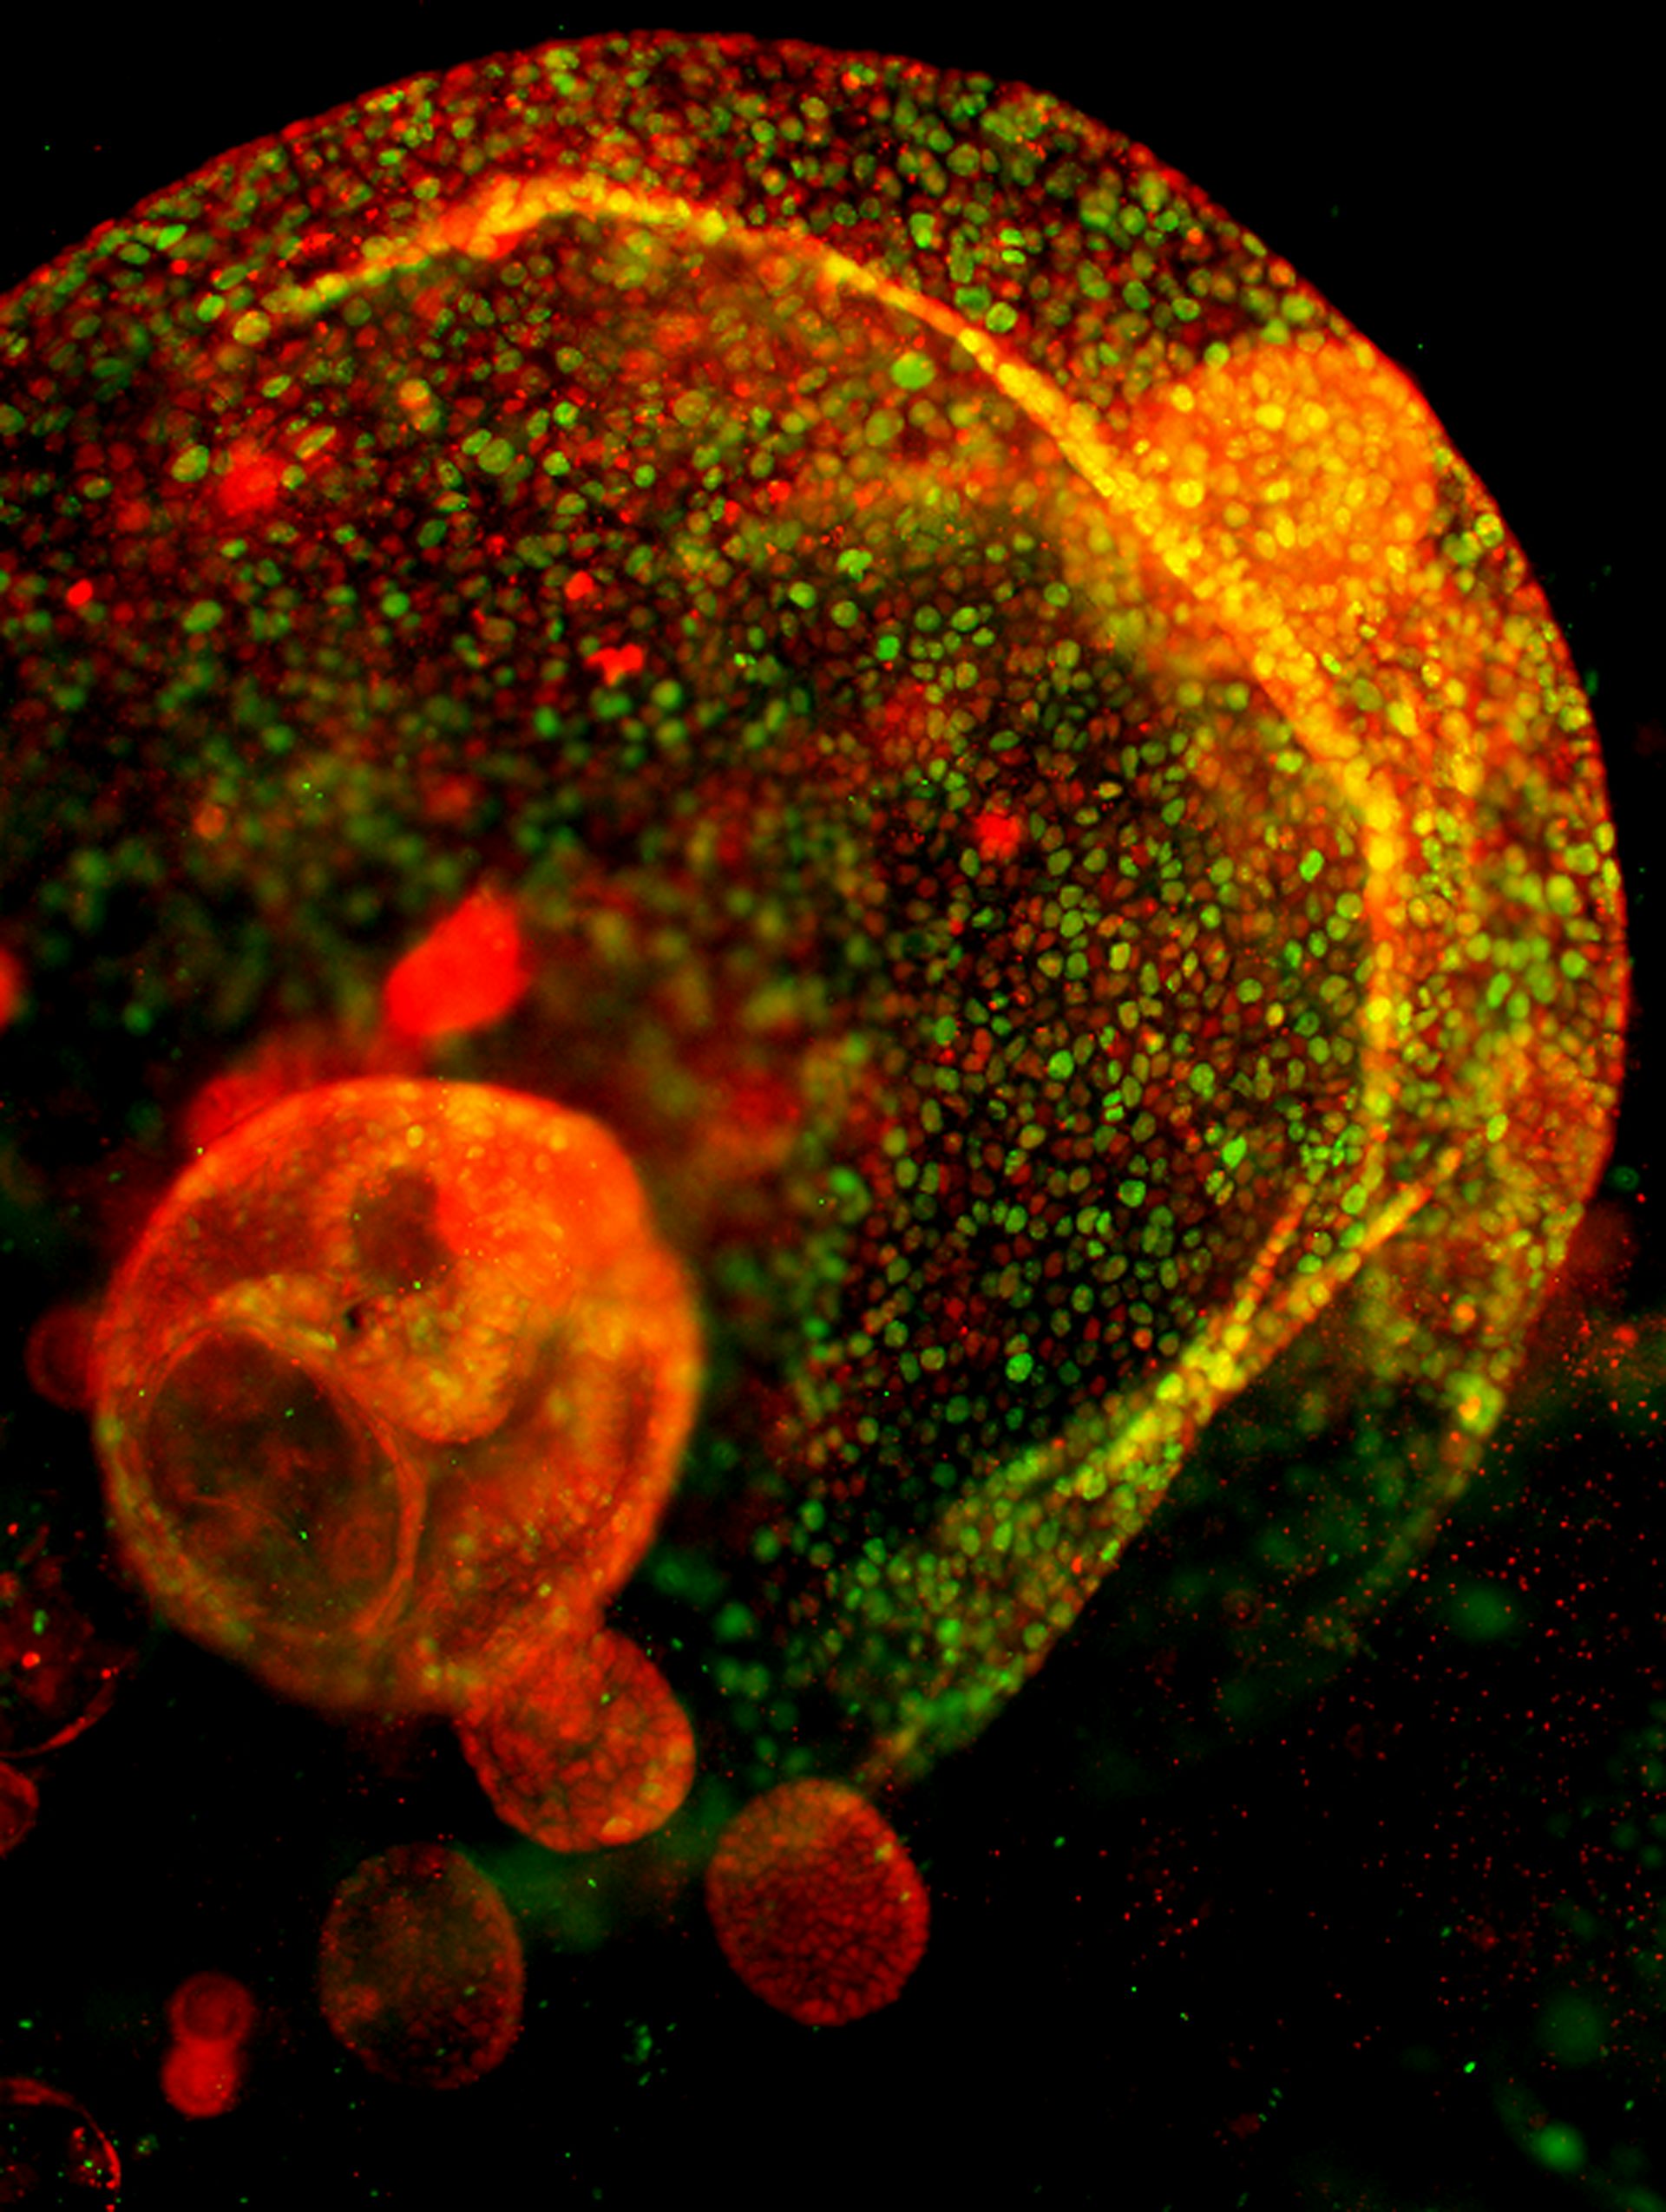

Organoides tridimensionales generados a partir de células epiteliales del conducto pancreático de ratón. (Habib Rezanejad)

Células ductales pancreáticas de ratón. (Habib Rezanejad)

En mi propia investigación, mi laboratorio cultiva organoides a partir de tejido pancreático humano y de ratón para estudiar la diversidad celular y la inflamación del páncreas. Estos modelos nos permiten investigar cómo se comportan los diferentes tipos de células pancreáticas en tres dimensiones, algo que sería imposible de observar en los cultivos tradicionales de células planas.